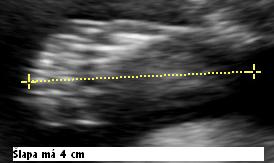

12/11 (14+3) sme boli v Medifere a pán doktor Holáň nám skoro hodinu vyšetroval všetky orgániky, či sme zdraví, videli sme srdiečko ako nám krásne bije, chrbátik aj ručičky a nožičky🙂)keď nám oznámil, že je všetko v poriadku veeeľmi sme sa tešili🙂)) ..hlavne budúci tato, ktorý bol na uzv prvý krát🙂 pan doktor nám povedal, že sme podľa neho popredu a on to videl na 15+3🙂))

Na konci vyšetrenia pán doktor len potvrdil to, čo si maminka myslela už dáávno, že to bude asi chlapček🙂 stráááášne sa tešíme

19.11. sme boli v Gin-Five na 3D uzv, bolo to super, lebo sme opät videli nasho chrustika, aj ked sa nam nechcel ukazt ani po dlllhej prechazdke po chodbe🙂)

21.12 2009 sme boli na velkom uzv u nasej pani doktorky a bolo to super hlavne pre buduceho tata 🙂 hned ako sa pozrela na anjelika, povedala, ze je to uplne jasne a je to chlapcek🙂))) vsak to sme skoro s istotou vedeli, ale teraz je to na 100 %🙂))) sme zdravi, trosku vacsi ako mame byt, mame dlhe nozky a viac plodovej vody🙂))

26 tt - GIN-FIV dr.Papcun - nas porodnik nam urobil krasne fotky nasho synacika najkrajsieho🙂)) nevieme sa nanho vynadivat🙂 Jakubko je otoceny hlavkou hore, ale snad si to do porodu rozmysli🙂)